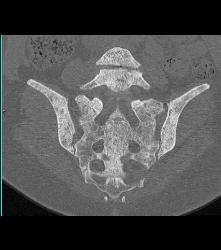

Psoas Abscess and IVC Clot